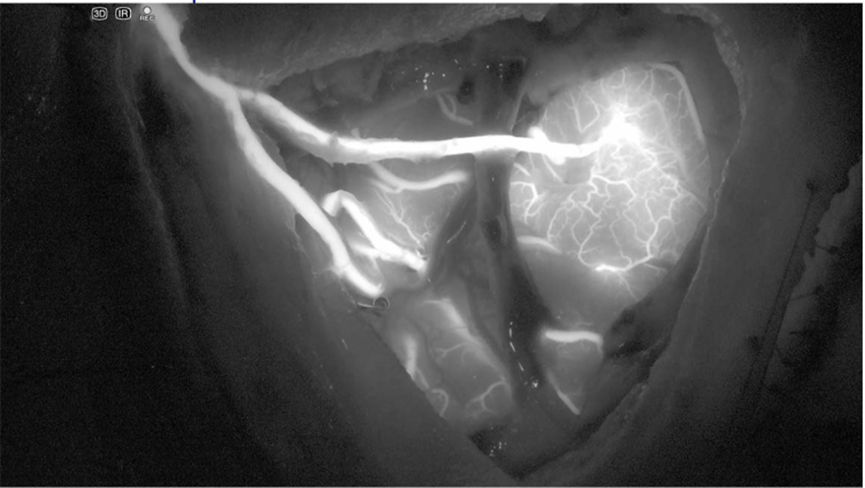

红外成像模式(ICG荧光):使用专用的LED能够直接产生所需要的波长,保证血管结构的ICG分布更加明亮,如图所示:

图 红外成像